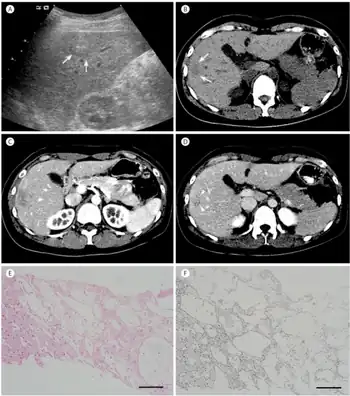

| The CT scan of a patient with peliosis hepatis (left): The follow-up CT (right) after 7 years shows full remission. | |

Peliosis hepatis is an uncommon vascular condition characterised by multiple, randomly distributed, blood-filled cavities throughout the liver. The size of the cavities usually ranges between a few millimetres and 3 cm in diameter.[1] In the past, it was a mere histological curiosity occasionally found at autopsies, but has been increasingly recognised with wide-ranging conditions from AIDS to the use of anabolic steroids. It also occasionally affects spleen, lymph nodes, lungs, kidneys, adrenal glands, bone marrow, and other parts of gastrointestinal tract.[2]

Two morphologic patterns of hepatic peliosis were described by Yanoff and Rawson.[13] In the phlebectatic type, the blood-filled spaces are lined with endothelium and are associated with aneurysmal dilatation of the central vein; in the parenchymal type, the spaces have no endothelial lining and they usually are associated with haemorrhagic parenchymal necrosis. Some consider both patterns to be one process, initiated by focal necrosis of liver parenchyma, observed in parenchymal type, progressing into formation of fibrous wall and endothelial lining around haemorrhage of phlebectatic type. Fibrosis, cirrhosis, regenerative nodules, and tumours may also be seen.